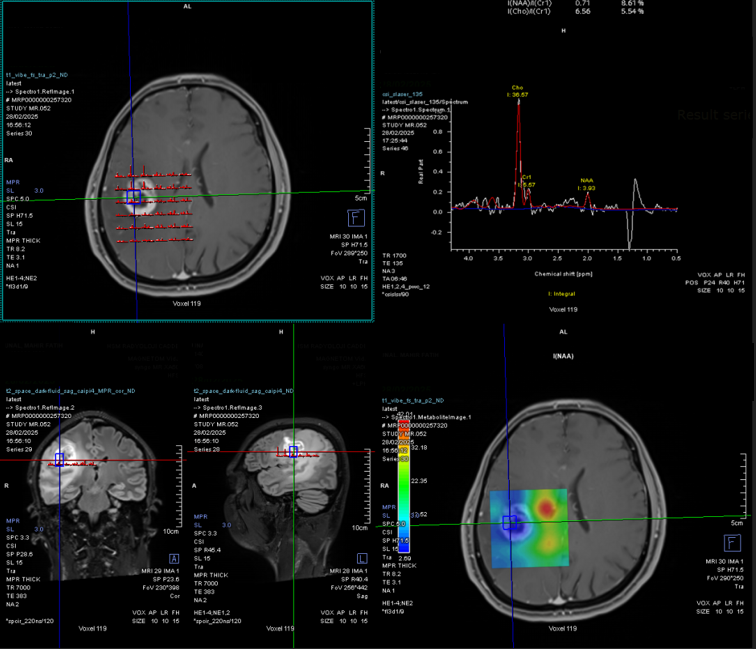

MR Spectroscopy (Magnetic Resonance Spectroscopy) is an advanced imaging technique that measures the chemical composition of tissues, providing critical information about the biochemical environment of the brain. Unlike standard MRI, which primarily focuses on anatomical structures, MRS analyzes the metabolic profile of brain tissue by detecting the concentrations of various metabolites, such as choline, creatine, N-acetylaspartate (NAA), and lactate. These metabolites can indicate changes in cellular metabolism that are associated with various neurological conditions, including tumors, infections, and degenerative diseases.

- Tumor Characterization: One of the primary uses of MRS in neurosurgery is in the differentiation of brain tumors. MRS can provide crucial information about the metabolic activity of a lesion, helping to distinguish between malignant and benign tumors. Malignant tumors typically show elevated levels of choline (a marker of cellular turnover), decreased levels of N-acetylaspartate (NAA) (a marker of healthy neuronal tissue), and the presence of lactate or lipids (which indicate tissue necrosis or hypoxia).

- Monitoring Treatment Efficacy: MRS is valuable for monitoring how brain tumors respond to treatments such as chemotherapy, radiotherapy, or targeted therapy. By comparing pre- and post-treatment metabolic profiles, it helps assess whether the tumor is shrinking, stable, or showing signs of recurrence. For example, a decrease in choline levels and an increase in NAA levels can indicate a positive treatment response, whereas elevated lactate levels may signal a lack of response or tumor progression.